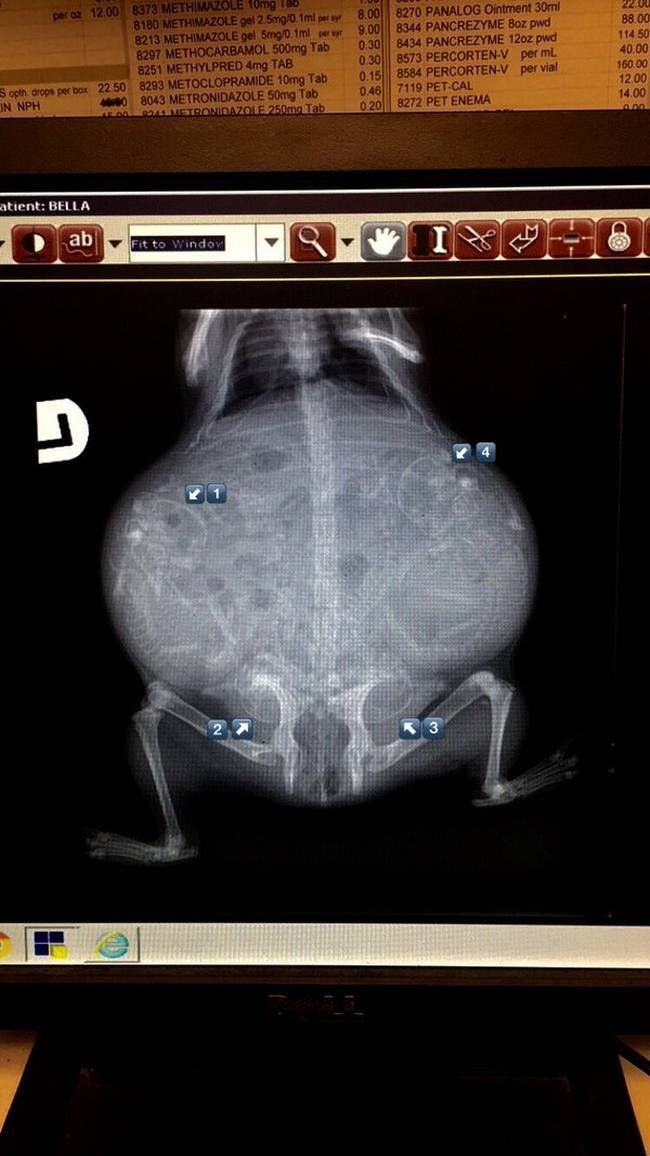

Рентген кошки с котятами в животике